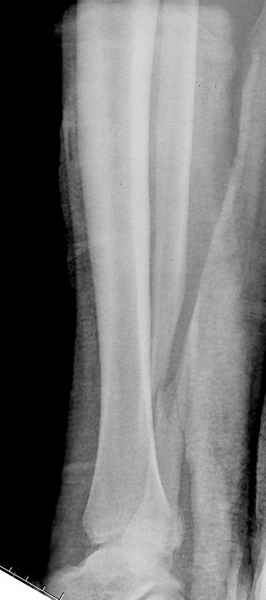

Здесь похожий случай трехнедельной давности, перелом почти сросся и была укорочена малоберцовая, на операции длину малоберцовой смогли восстановить только после того, когда проксимальнее пластины ввели шуруп и использовали его как толкатель, с помощбю дистракционого инструмента (lamina spreader).

При реконструкции голеностопа, о важности восстановления длины малоберцовой для профилактики пост травматического артроза разбирали в предыдущих дискуссиях. Нарушенную биомеханику голеностопа без восстановления длины малоберцовой, не восстановить только швом медиальной связки.

Расширенная медиальная щель более чем на 4 мм и укорочение малоберцовой более чем 2 мм, а перелом заднего края большеберцовой смещения более 2мм с вовлечением 30% поверхности сустава, считается отходом от нормы голеностопного сустава, и подлежит к оперативному вмещательству.